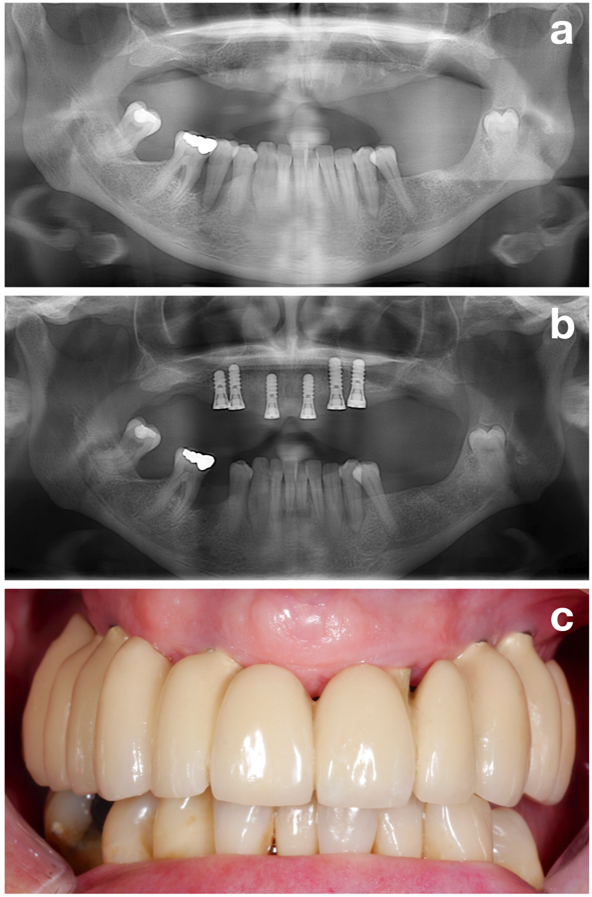

The NIWOP concept (Figure 1) is split into 3 major aspects: (1) Pre-treatment phase, (2) implant installation, and (3) recall or supportive treatment.

The first part (i.e., the pre-treatment phase) aims to perfectly prepare the patient for the actual implant installation by evaluating all potential risk factors but focusing on one of the most important ones: establishment of a stable periodontal situation (Figure 2).

In conclusion, establishing a stable periodontal situation is next to other aims, such as smoking cessation or perfect oral hygiene (Figure 3), one of the most important goals in the pre-treatment phase, which should be achieved prior to implant installation!